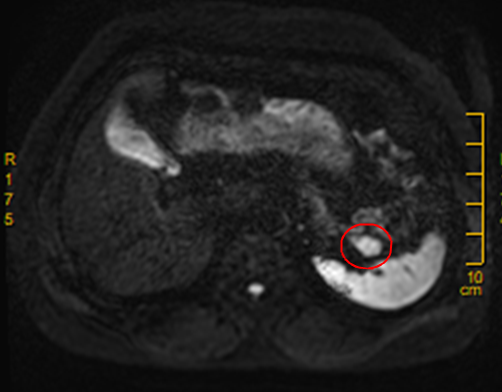

经过磁共振检查后仔细阅片,放射科医生发现张阿姨的胰腺尾部的确是长了一个类圆形的小肿瘤。

磁共振片

张阿姨随后转到肝胆胰外科进行腹腔镜下病灶切除手术,术中在胰腺尾部切除一个直径约2.5cm大小的肿瘤,术后的病理报告证实是胰岛素瘤(一种功能性胰岛细胞瘤)。